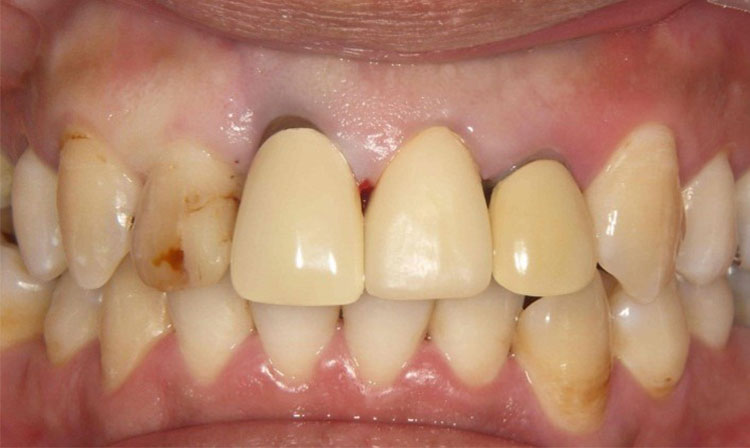

All-on-4症例 Case1

Treatment cases

Before

After

インプラント治療は、咀嚼機能の改善だけでなく、 口腔周囲筋の発達により見た目の若返りにも貢献してくれます。